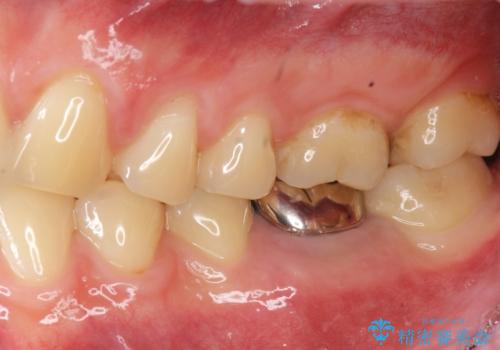

銀歯・レジンコアを除去したところ、薄い残存歯質に亀裂が入り、保存が難しい状況が認められました。

歯を残すことが難しい状況であることの説明、抜歯の提案を行い、抜歯後はブリッジ・入れ歯ではなくインプラント治療を希望されました。